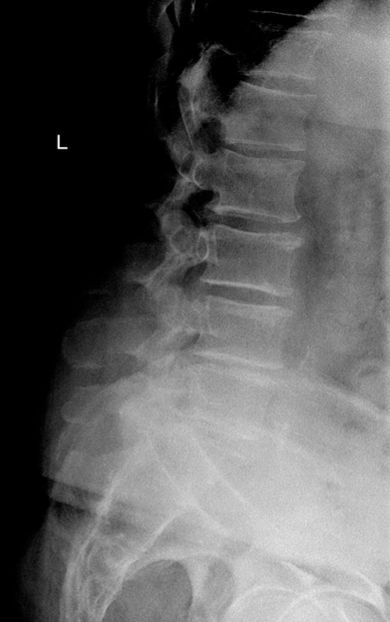

Rad - Spondylosis

ant or post osteophytes

narrowed disc space

scoliosis, lordosis, kyphosis

MRI, CT, X-ray